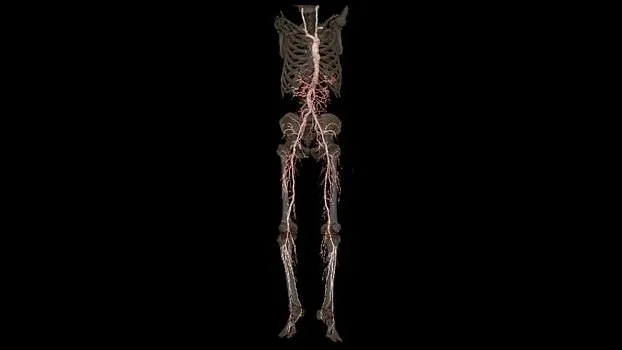

Клинические изображения

Технология TrueFidelity

Revolution Ascend поддерживает технологию TrueFidelity**, которая реконструирует изображения с помощью алгоритмов глубокого обучения. Она обеспечивает глубокую детализацию, естественную текстуру, высокую контрастность и четкость изображений. TrueFidelity генерирует изображения с помощью алгоритмов искусственного интеллекта. Это позволяет, с одной стороны, использовать низкую лучевую нагрузку, как при итеративной реконструкции, а с другой стороны, получать изображения, не уступающие по качеству методу фильтрованных обратных проекций.